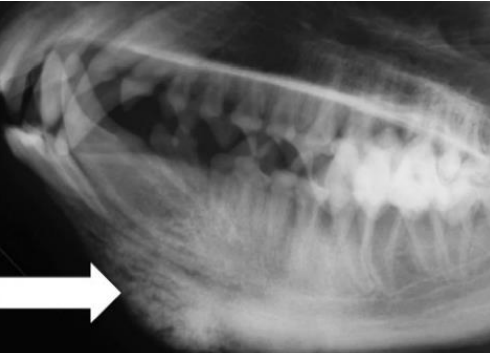

![]() ![]() | - caudal mandibles의 irrecular bone density가 증가. - tympanic bullae의 밀도도 증가. - 1/3의 환자는 mandible에 국한된 병변을 보이지만, 일부 경우 skull의 바닥에 병변, 또는 두개골 자체가 비대(thickened calvarium). - 개가 성숙해 가면서, 새로운 뼈의 가장자리가 매끄러워지고, 비정상 부위가 줄어듦. |